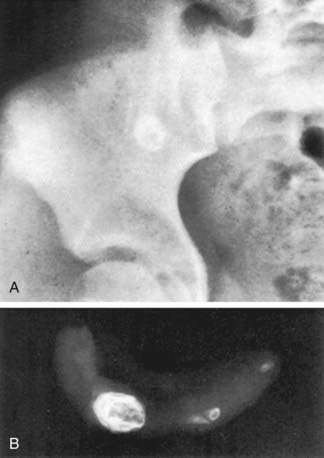

CT scan has been the gold standard imaging study for evaluating children with suspected appendicitis. CT examination can be performed in many ways, including standard CT scan, helical CT scan, with or without oral and intravenous contrast, examination of both the abdomen and pelvis or pelvis alone, focused appendiceal CT scan, and focused appendiceal CT scan with rectal contrast. All of these techniques have demonstrated >95% sensitivity and specificity for acute appendicitis. Findings on CT scan consistent with appendicitis include a distended thick-walled appendix, inflammatory streaking of surrounding mesenteric fat, or a pericecal phlegmon or abscess (Figs. 335-3 and 335-4).

image

Figure 335-3 A, Phlegmon (open arrow) is noted around the enlarged appendix (solid arrow) in perforated appendicitis. B, Extraluminal air is shown adjacent to the wall-enhanced appendix (arrow) in perforated appendicitis.

(From Yeung KW, Chang MS, Hsiao CP: Evaluation of perforated and nonperforated appendicitis with CT, J Clin Imag 28:422–427, 2004.)